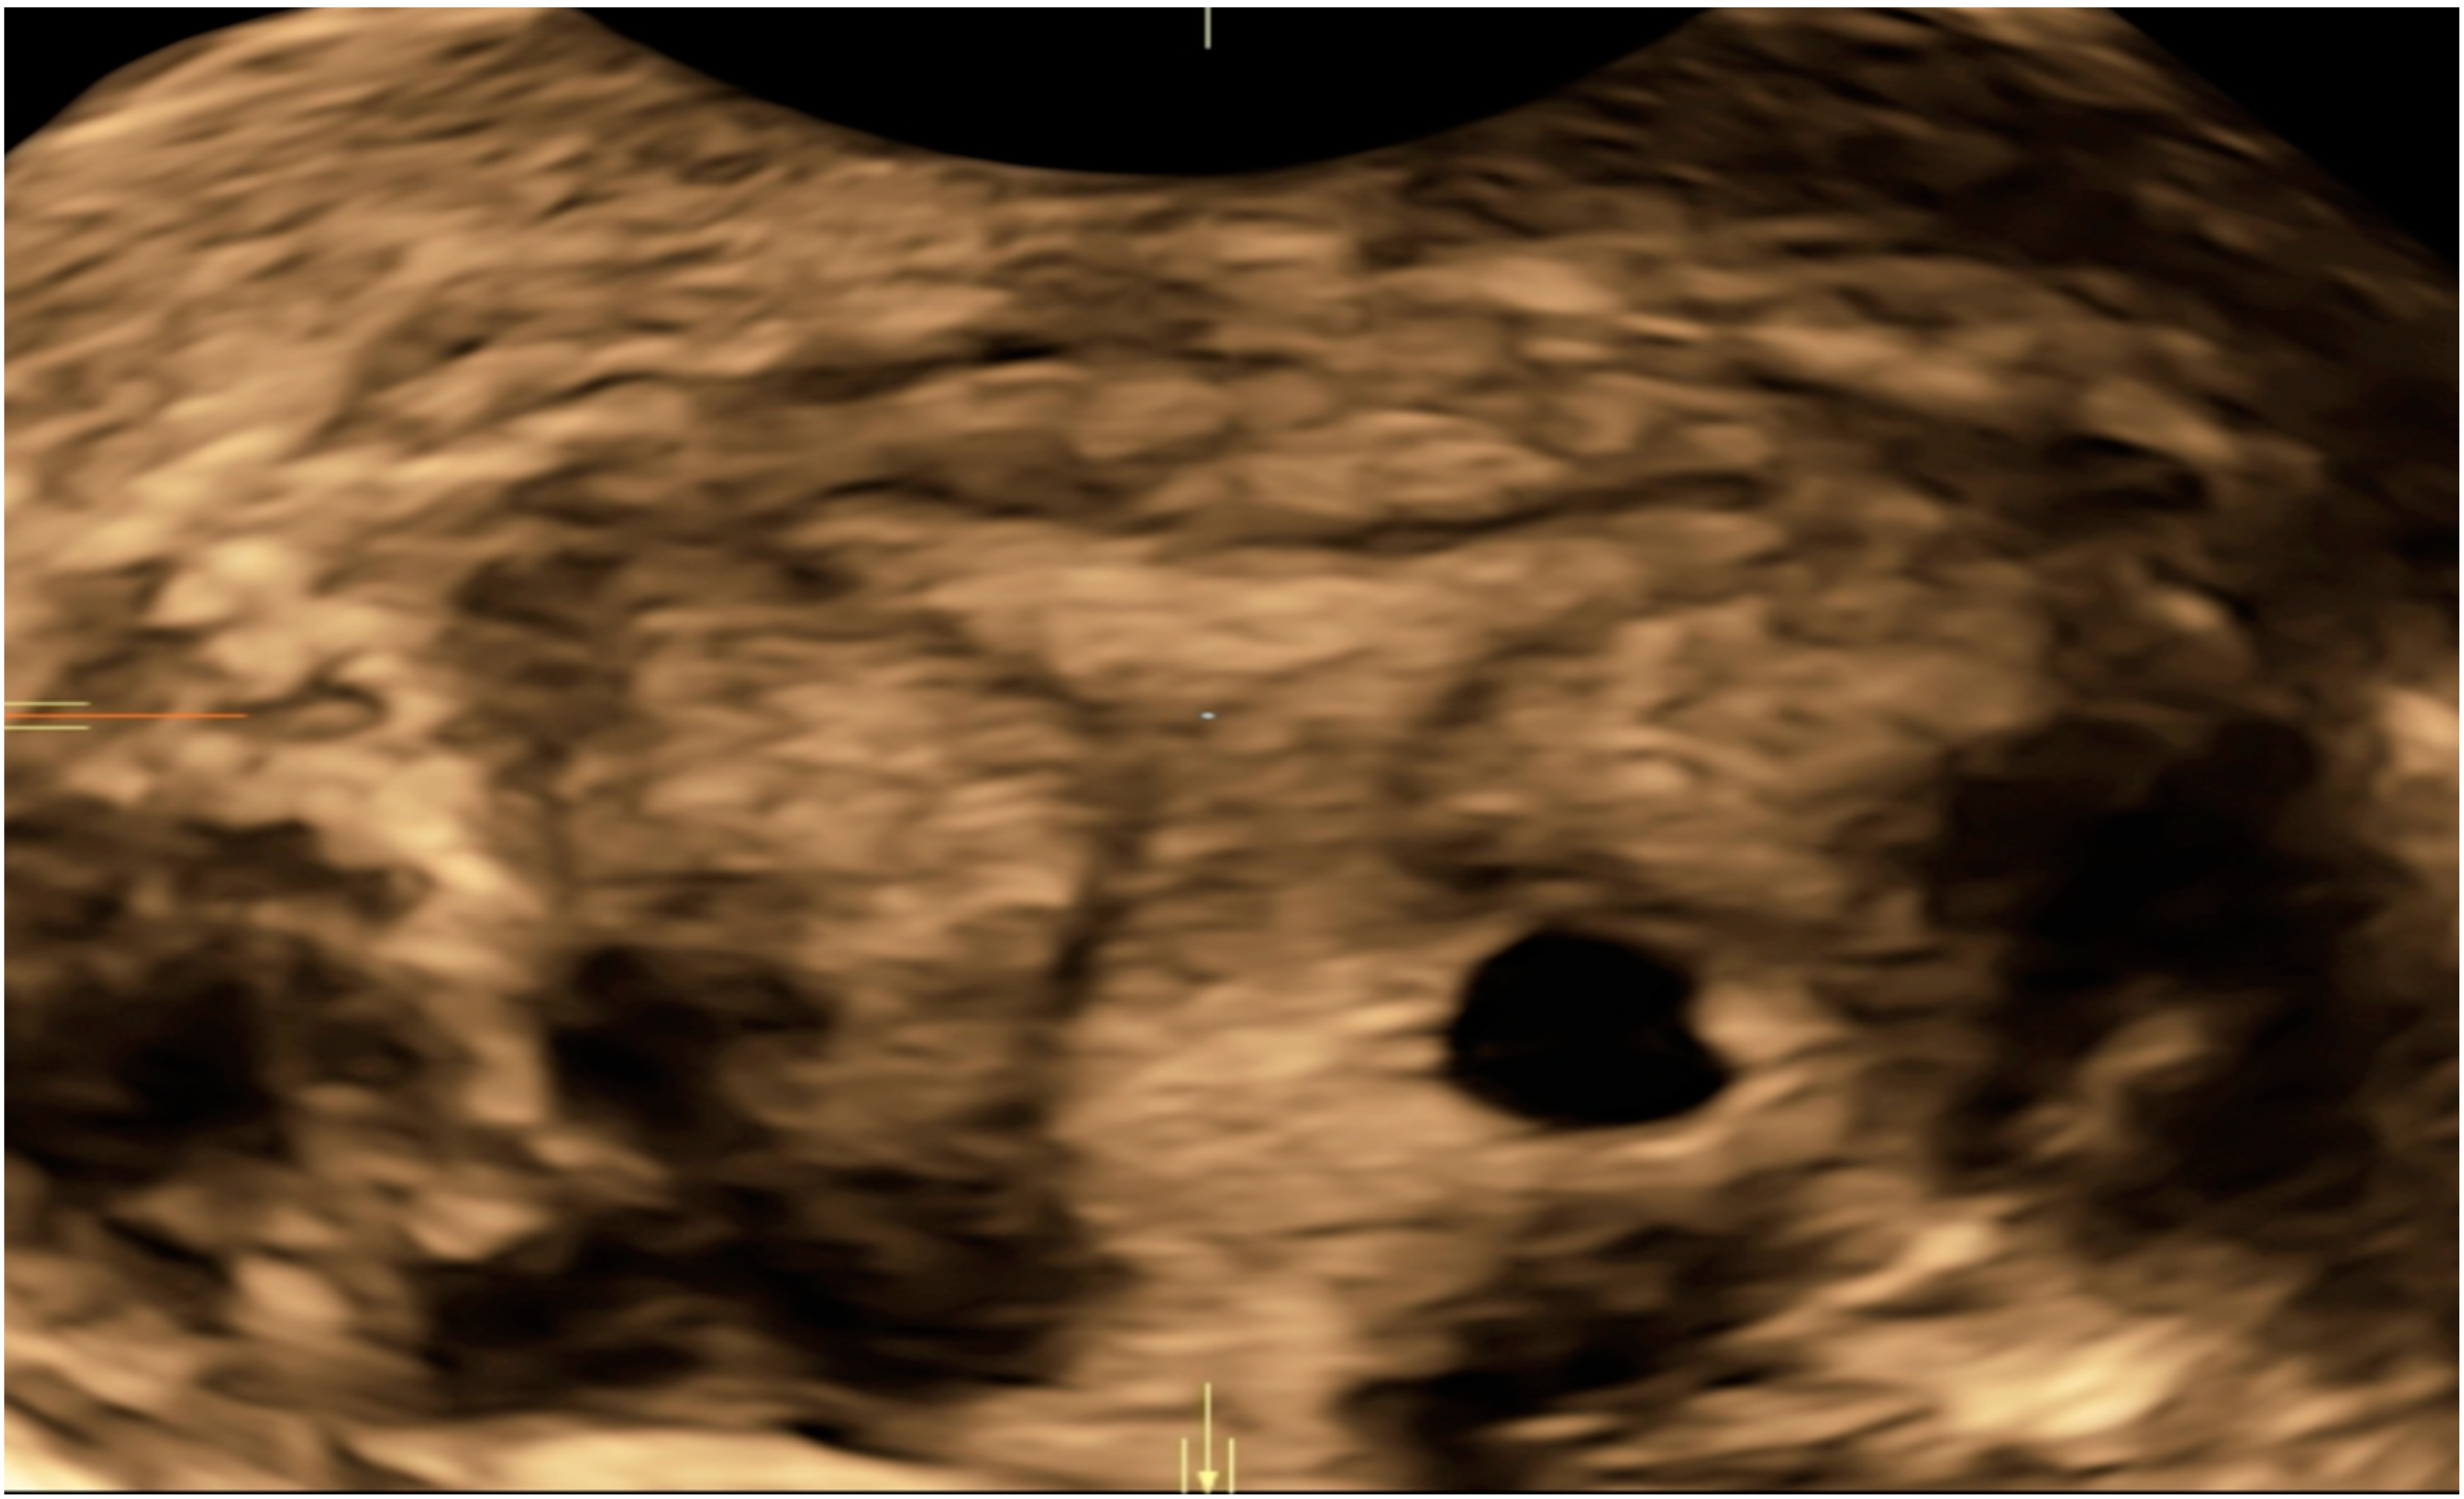

| Case 2 | Asymptomatic | 6 + 6 | 10,862 | GS 20 × 19 mm; with embryo | Hys: 1st step: CP resection by twizzle; IC Foley catheter 2nd step: vessels electrocoagulation by bipolar twizzle  | Reoperation (hys) due to tissue residues and cervical laceration Complete resolution  |

| Case 3 | Asymptomatic | 5 | 9747 | GS 20 × 22 mm; no embryo | MTX IM 50 mg/m2 of body surface + Hys | Complete resolution Currently pregnant (PMA Homologous)  |

| Case 4 | Brownish vaginal discharge | 6 + 6 | 55,951 | GS 30 × 10 mm; no embryo | Hys | Complete resolution |

| Case 6 | Vaginal bleeding | 6 | 4274 | GS 5.4 × 5 mm with embryo | MTX IM 50 mg/m2 of body surface + Hys: CP resection by twizzle  | Complete resolution |

| Case 1 | Asymptomatic | 6 | 119,900 | GS 14 × 16 mm | MTX IM 50 mg/m2 of body surface + Misoprostol 200 µg rectal + Hys (two times) + Curettage | Complete resolution |

| Case 2 | Asymptomatic | 6 + 2 | 31,647 | GS 12 × 10 mm | Mifepristone 600 mg + Misoprostol 400 mcg + Hys: reseptoscopy | Complete resolution |

| Case 3 | Asymptomatic | 7 + 1 | 131,000 | GS 9 × 10 mm | Hys: twizzle and minireseptor + Curettage  | Complete resolution |